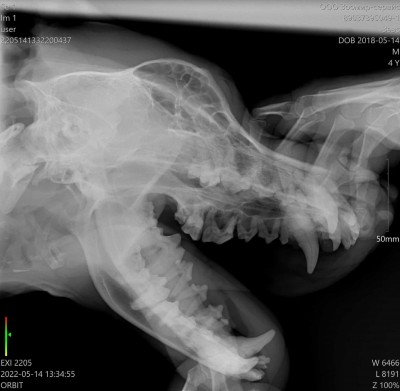

Расковыряла болячку под глазом.

Думаю мое первое ощущение правильное, это свищ.

Значит при кастрации еще и зуб удалять.

Хочу сделать ему рентген, глянуть на глотку, пищевод и трахею и, наверное, подавать флюкостат(флюконазол). Он за последний месяц только попав под наше крыло получал антибиотики трижды: что-то у волонтеров от простаты, амоксициклин после операции и бисептол.